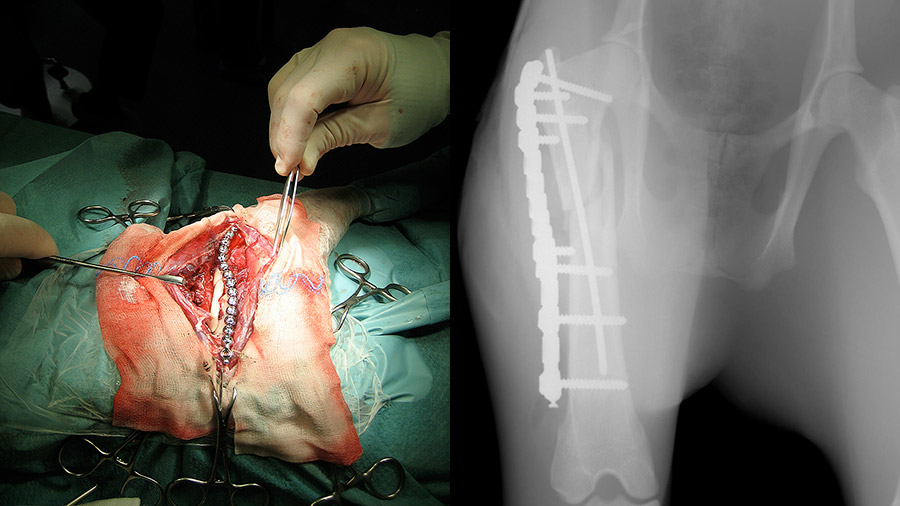

“Because so little is known about pudu anatomy, I did the approach that I knew from operating on dogs and it actually was not much different. I was more concerned by the fact that she was pregnant, that I really had to achieve stable fixation, and that she was a ruminant animal requiring an air tube to her stomach because ruminant tend to gas up and get stomach distension that can be dangerous,” Jopp said.

Over the course of the two-hour surgery and assisted by Prof Walter Brehm, Universität Leipzig Head of Equine Surgery, Jopp reduced the pudu’s fracture as much as possible, applied a pin inside the bone to guarantee correct length and alignment, and then applied a locking “string of pearls” (SOP) plate to stabilize the bone.

“I wanted something very stable because this was a very proximal fracture. Also, pudu bones are quite brittle, so we needed as many screws as possible and good fixation between the plate and bone in order to achieve a stable environment for healing,” she said.

Despite the high stakes—Esta was one of just three remaining pudus at Zoo Halle after a viral infection swept through its herd—having the AO Principles as her guide inspired Jopp’s confidence.